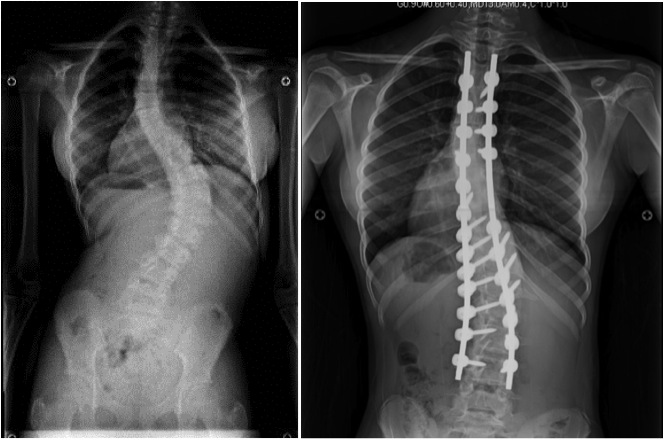

Коррекция позвоночника с помощью хирургического вмешательства используется на запущенных стадиях недуга, когда остальные методы уже не помогают. В процессе операции устанавливают специальные фиксаторы и протезы. Чем опасна операция? Тем, что предстоит длительный период восстановления и возможно проявление осложнений. В процессе операции участки, которые не поддаются исправлению, заменяют специальными титановыми фрагментами.